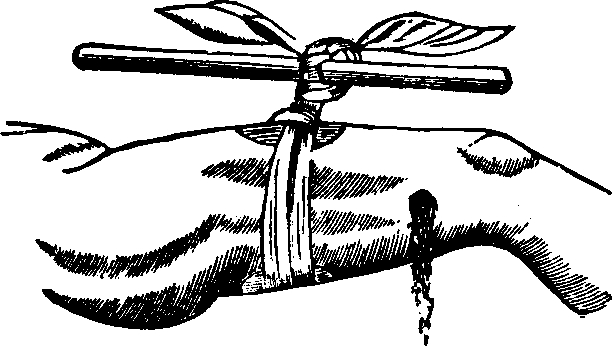

How to Use Vaginal Injections. We usually recommend the Fountain Syringe illustrated in Fig. 6, as the most convenient instrument for administering vaginal injections. The fountains supplied by us are of soft rubber, and have extra nozzles, with which to make rectal, nasal or ear irrigations. There is also a large, long nozzle for vaginal injections.

Fig. 7. SOFT RUBBER-BULB SYRINGE

It is channeled so is to permit the free clearing [pg 706]away of the secretions as the Douche is employed. The Fountain Syringe can he used without assistance, the flow of fluid is gradual, and with a force that can be varied, by raising or lowering the reservoir, yet is never so great as to be liable to produce injurious effects.

The syringes usually sold with small nozzles or pipes are of little or no value for vaginal injections. In many instances so small a tube will pass readily into the canal of the uterus, and hence there has frequently resulted an injection of a portion of the fluid into the uterus itself, producing severe pain. It is important, therefore, in using the Vaginal Douche to employ only a large tube that has grooves in its surface for the free clearing away of the fluid as it runs from the fountain.

Where it is desired to obtain relief from a congested, inflamed or sensitive and irritable state of the mucous surface, the employment of a large quantity of water as hot as it can be borne, is of the greatest remedial value. It rapidly diminishes the size of the blood vessels, and aids in bringing about a normal circulation in the parts.

As a rule, in taking the Douche with the Fountain Syringe the rubber bag is filled, and suspended from a nail or hook at a height of from two to five feet above the patient, and the fluid passes through the tube by force of gravity, thus requiring no muscular exercise. The force of the stream depends upon the height of the fountain above the outlet nozzle. It is only necessary that the patient should assume a comfortable position where the fluid which comes from the vaginal canal can flow into a water closet, or any convenient vessel.

After a thorough cleansing of the vaginal surfaces of mucus, by means of the warm or hot water, it is sometimes advisable to inject remedial fluids. These injections may readily be made with the fountain or bulb syringe, introducing not less than from two to four ounces. This may be retained sufficiently long to exert its remedial effects upon the mucous surface, which usually takes from five to eight minutes. The hips should be elevated, and the nozzle of the syringe surrounded by a napkin or other similar material, upon which moderate compression can be made so as to retain the fluid in the vagina for the necessary period.

To those who are unable readily to obtain the Fountain Syringe above recommended we can send by mail, post-paid, one of these instruments on receipt of $2.00.

A Soft Rubber-bulb, or Pump Syringe (illustrated in Fig. 7), not so good for making vaginal injections, can be sent by us, post-paid, for from 75cts. to $1.50, the price varying with the quality and size.